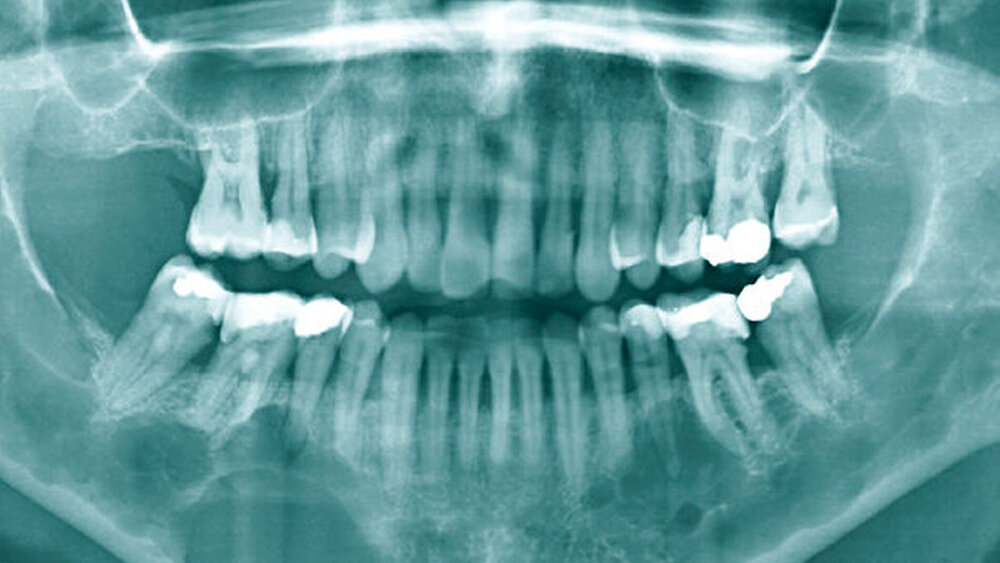

Das Orthopantomogramm zeigte eine auffällige, homogene, scharf begrenzte osteolytische Veränderung in regio 43 bis 46 ohne Resorption der angrenzenden Zahnwurzeln, allerdings mit Destruktion der Corpusunterkante korrespondierend zur klinisch evidenten Auftreibung des Unterkiefers. Daneben waren weitere osteolytische Läsionen zu verzeichnen, die sich subtotal über die gesamte Mandibula verteilten (Abbildung 1). Die Computertomografie des Unterkiefers bestätigte das Vorliegen multipler disseminierter osteolytischer Prozesse (Abbildung 4).

Als erste Symptome im Krankheitsverlauf der Patientin sind die Auftreibung im Bereich des Unterkiefers und die in der zahnärztlichen Röntgendiagnostik auffälligen osteolytischen Veränderungen anzusehen. Im Rahmen einer Zahnfilmaufnahme kann eine solche apikale Osteolyse fälschlicherweise als Parodontitis apikalis chronica oder radikuläre Zyste gedeutet werden. Das Orthopantomogramm ist bei großen Raumforderungen als Übersichtsaufnahme besser geeignet und unnötige Trepanationen können vermieden werden. Die im Orthopantomgramm der Patientin dargestellten, nahezu über den gesamten Unterkiefer disseminierten multiplen Osteolysen erscheinen ungewöhnlich und untypisch für die in der Zahnheilkunde bekannten zystischen Formationen.